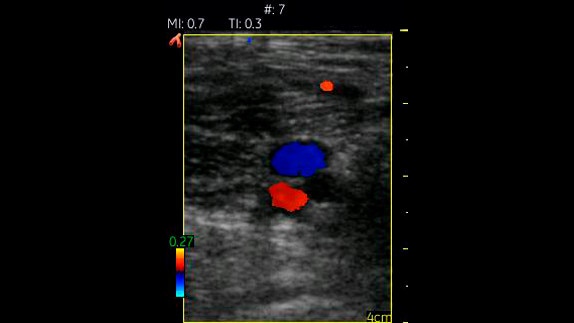

Vasküler